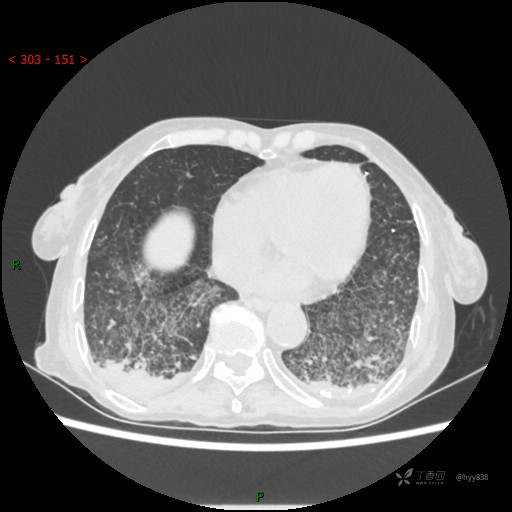

肺部弥漫性、疑难病变,感染或肿瘤?一元论或二元论?贴贴精彩---结果公布~

简要病史:患者10余天劳累后出现发热,最高体温达39.5℃,无畏寒、寒战、鼻塞、流涕,无头晕、头痛,无心慌、胸闷、胸痛,无咳嗽、咳痰、气喘,无反酸、烧心、恶心呕吐,无腹痛、腹胀等不适,于2022-5-31至当地中医医院住院治疗,诊断为重症肺炎,予以抗感染、抗病毒等对症支持治疗,仍反复发热,现为求进一步诊治,至我院门诊就诊,门诊以“重症肺炎”收入我科。 起病以来,患者精神、饮食、睡眠差,大小便正常,体力下降,体重无明显变化。

临床诊断:重症肺炎

胸部CT平扫